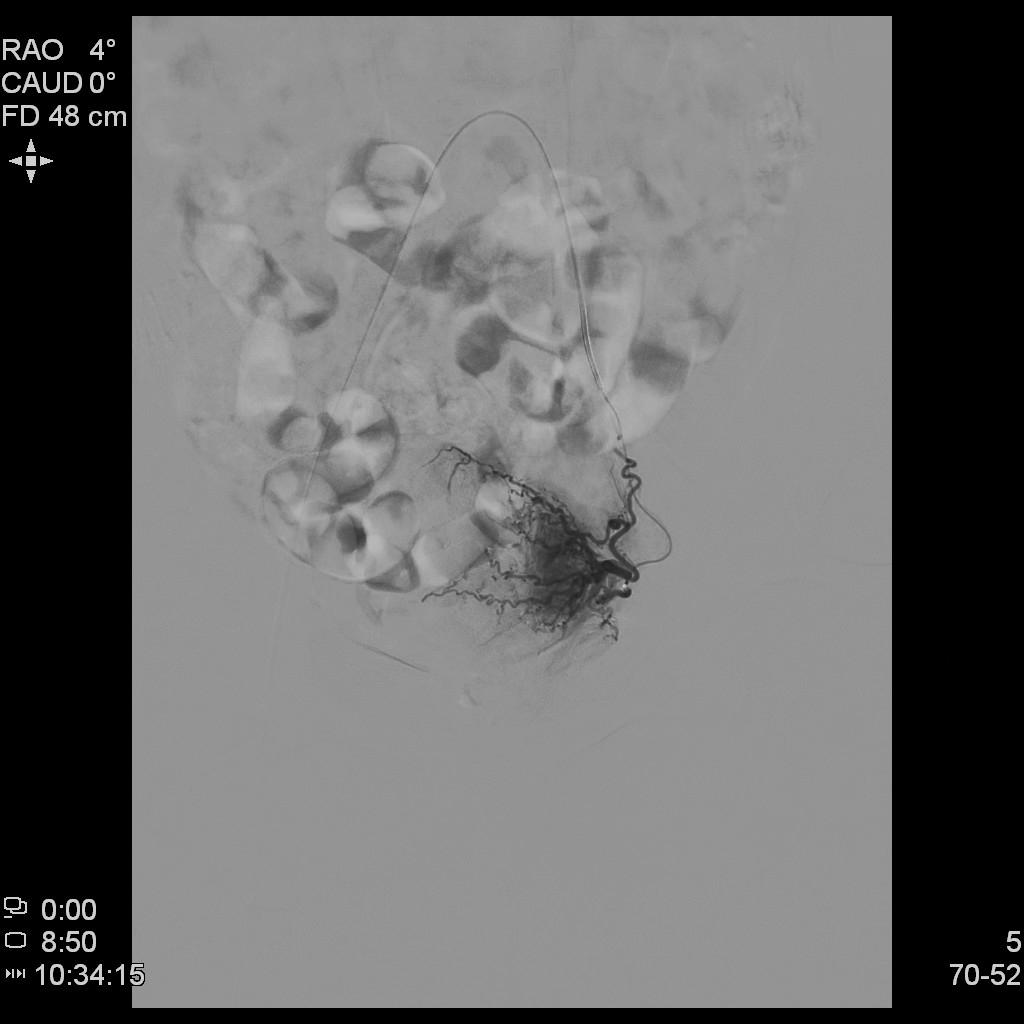

- 插管至右侧子宫动脉,显示子宫右侧病灶情况

右侧子宫动脉造影

左侧子宫动脉造影